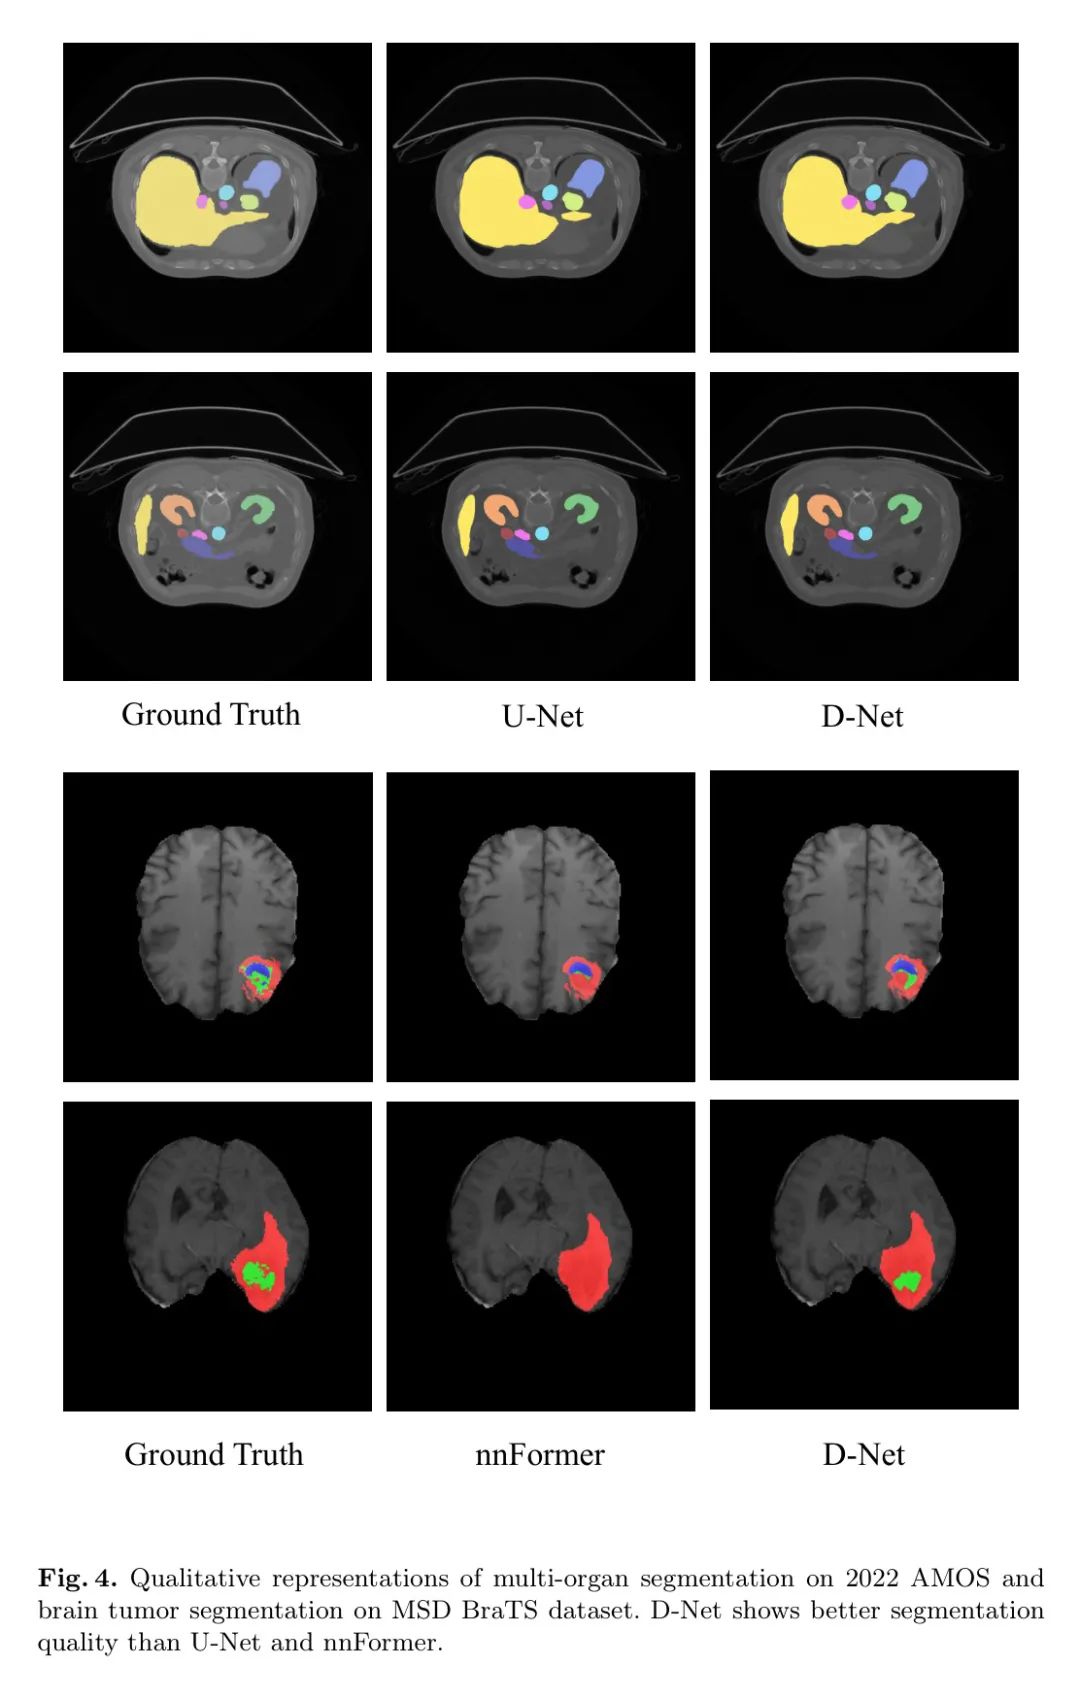

表1展示了在AMOS腹部多器官分割任务上的性能对比。D-Net以相对较少的FLOPs和最低的参数数量取得了最佳的整体性能。此外,D-Net在所有特定器官分割任务中的Dice得分都有显著提升。

表2展示了MSD脑肿瘤分割任务的结果。与其它分割方法相比,D-Net在所有分割任务上都展示了优越的性能。